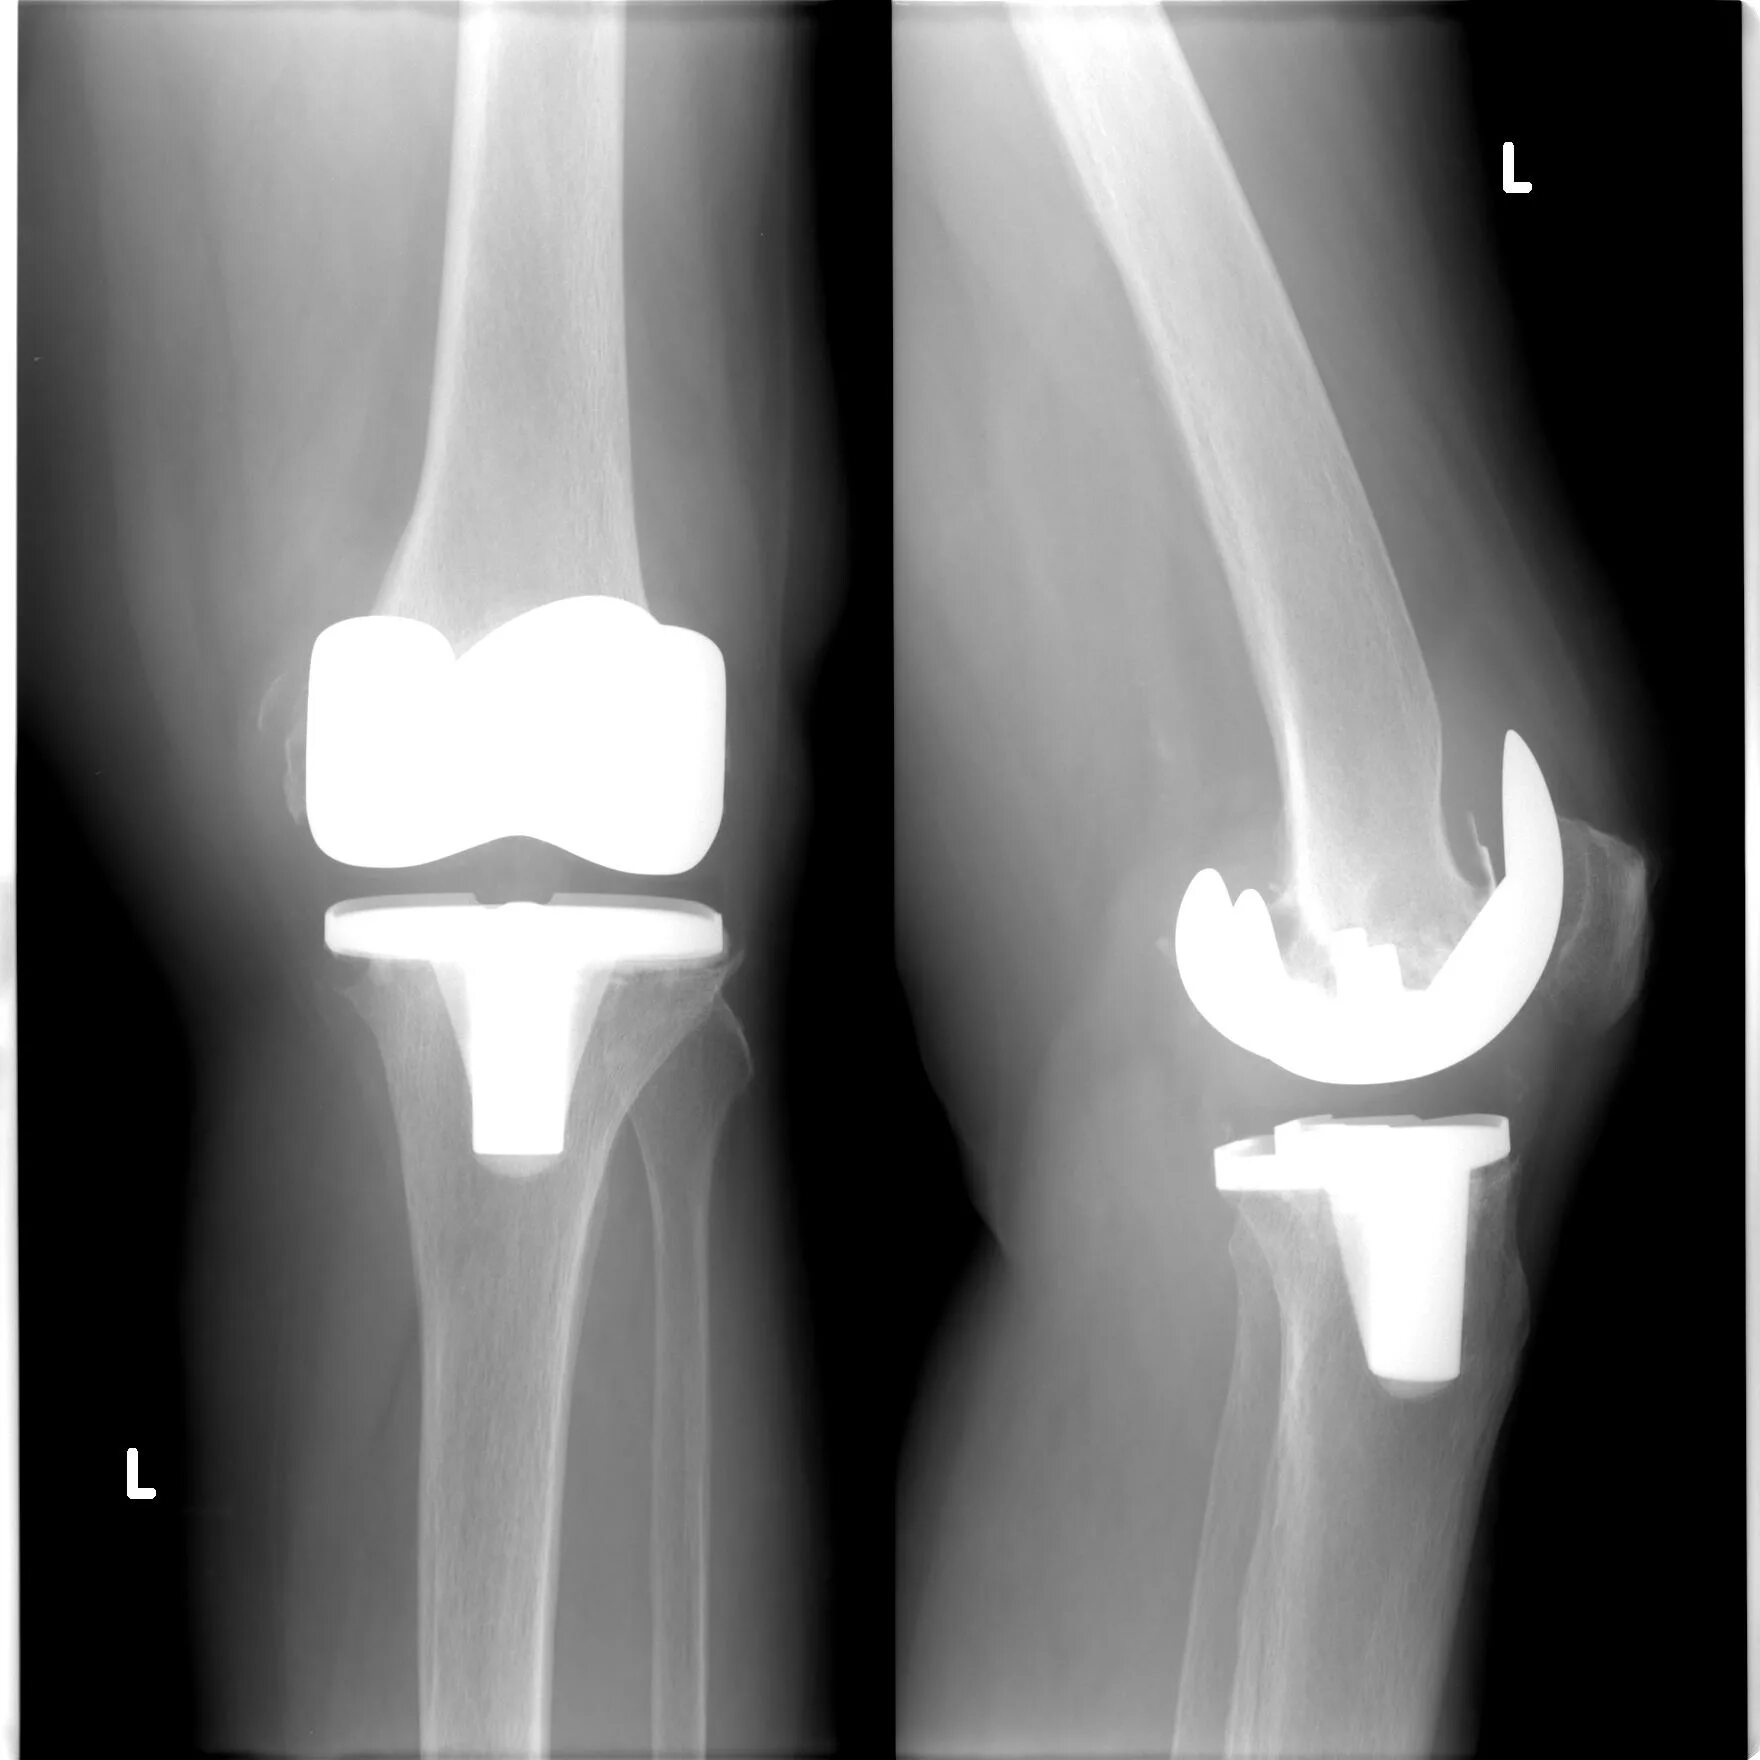

После тотального эндопротезирования коленного сустава